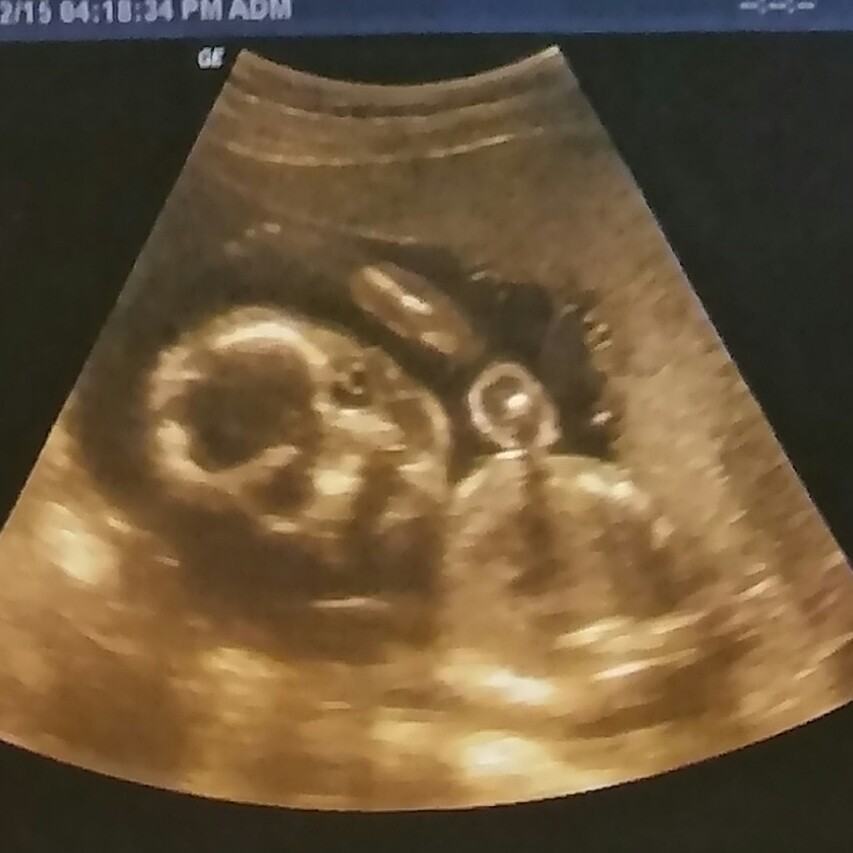

Boy or girl?

The tech showed us a clear view of "the bladder", as if we were infront of the baby looking between the legs. Very clearly no nub of any kind, so I got excited! BUT they didn't put that shot on our disk, sooo...any guesses on female or male based on what I have? Week 12 Attachment 30649